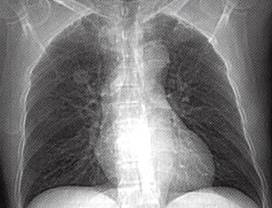

图1肺错构瘤

A

A.X线胸片示右上肺野孤立结节,边缘光整;

1)周围型:多为孤立性肺结节,少数为较大肿块,病灶边缘光整,无分叶,部分病灶内见钙化,典型钙化呈“爆米花样”。